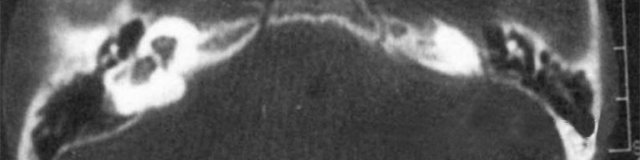

主要依靠顳骨高分辨CT和內(nèi)耳MRI。

雙側(cè)內(nèi)耳畸形:左側(cè)無內(nèi)耳迷路及內(nèi)耳道機構(gòu),為米歇爾畸形;右側(cè)空耳蝸及前庭擴大,為先天性耳蝸畸形